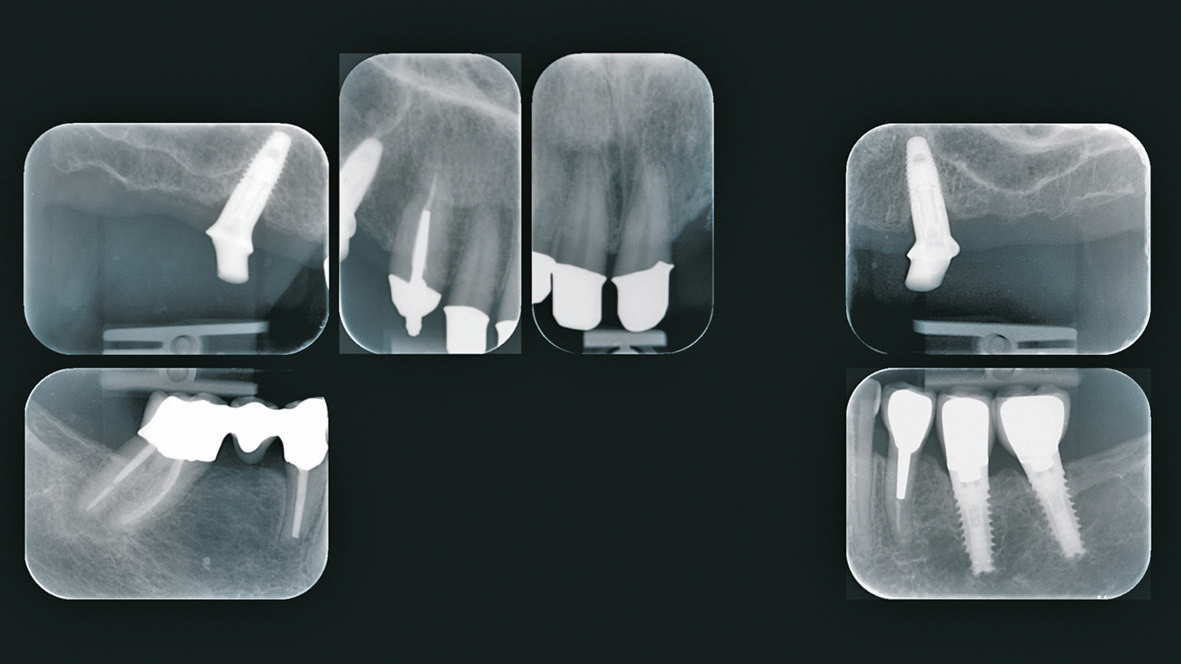

Die seinerzeit 68-jährige Patientin stellte sich im Jahr 2015 in der Klinik für Rekonstruktive Zahnmedizin und Myoarthropathien an den Universitätskliniken für Zahnmedizin in Basel vor, mit dem Wunsch nach einer langfristig stabilen Versorgung im Oberkiefer. Sie war im Oberkiefer mit einer bereits mehrfach angepassten alio loco hergestellten Teilprothese versorgt. Die medizinische Anamnese war unauffällig. Die Mundhygiene der Patientin war bereits zu dem Zeitpunkt auf einem guten Niveau und die parodontale Situation war abgesehen von lokalisiert leicht erhöhten Sondierungstiefen um den längsfrakturierten Zahn 22 sowie beim Implantat in regio 35 stabil. Neben den verblockten Kronen 13-12-11-21 wurde auch die gemischt zahn- und implantatgetragene Brücke 34-35i-36i-x aufgrund mangelhafter Passgenauigkeit als erneuerungsbedürftig eingestuft. Die definitive Neuversorgung im Unterkiefer sollte jedoch auf Wunsch der Patientin bis zum Abschluss der Versorgung im Oberkiefer aufgeschoben werden. Die über 20-jährige Brücke 34-x-36 konnte hingegen sowohl klinisch als auch radiologisch als suffizient eingestuft werden (Abb. 1 u. 2).

Nach Abschluss der Vorbehandlung erfolgte die Implantatplanung. Dazu wurde die neu angefertigte ideal ausgerichtete Drahtklammerprothese dubliert und das Duplikat als Röntgenschablone verwendet. Mithilfe der Planungssoftware NobelClinician ® (Nobel Biocare, Göteborg, Schweden) wurden möglichst weit distal und damit unmittelbar vor dem Sinus maxillaris zwei Implantate in regio 15 und 25 geplant (Abb. 6). Anschließend wurde die Röntgenschablone im Bereich der geplanten Implantatpositionen angepasst, sodass sie als Orientierungshilfe bei der Implantation verwendet werden konnte (Abb. 7). Die Implantationen erfolgten unter Lokalanästhesie in einer Sitzung. Es wurde ein geschlossenes Einheilverfahren gewählt. Zur postoperativen Kontrolle der Implantatpositionen wurde eine Orthopantomografie angefertigt (Abb. 8).